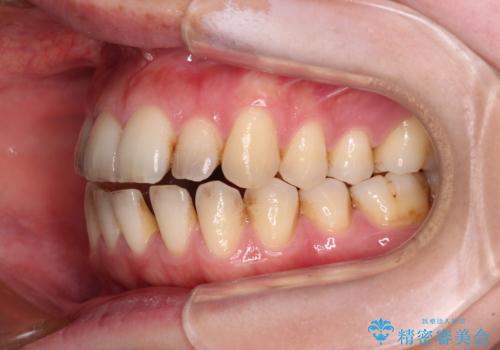

- 上下前歯の隙間を気にして来院された患者様です。

下顎前歯が1本欠損しており、上下小臼歯はクロスバイトとなり、上下前歯の接触もないという不正咬合の状態でした。

クロスバイトはワイヤー矯正が得意とするところであり、上下前歯の非接触や開咬はインビザラインの得意とするところであるので、ワイヤー装置により事前にクロスバイトを改善し、その後にインビザラインにて仕上げていくこととしました。

奥歯の咬み合わせに問題がある場合、インビザラインでは改善できないことが多々あります。事前にワイヤー装置により問題点を解消しておくことで、スムーズにインビザラインでの矯正治療を進めていくことができます。